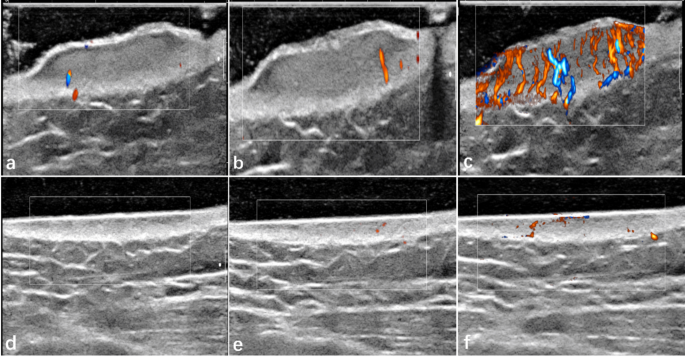

Furthermore, blood flow levels assessed in the AP mode displayed significant variations, as shown in Fig. 1g-i. The AP mode could differentiate between the mild-moderate and mild-severe groups (P = 0.045 and P = 0.05, respectively). Mild keloids showed almost no vessels, while severe keloids exhibited abundant blood flow signals with a high vessel presence. Whereas the CDFI and PDI modes only distinguished the mild-moderate group (P < 0.001 and P = 0.004, respectively). All the blood flow gradings are shown in Table 1. In addition, the evaluation of vascularity within keloids using three different color flow modes yielded significant findings. The AP mode detected blood flow signals that exhibited statistically significant differences between untreated and treated patients (P < 0.001, as shown in Table 2). Figure 3 visually illustrates this observation, demonstrating that as the blood flow grade increases, the quantity and richness of blood flow signals correspondingly increase. However, the blood flow grading detected by CDFI and PDI modes did not show significant differences. This highlights the sensitivity of the AP mode in detecting changes in microvascular blood flow, providing valuable insights into the evolving status and activity of keloids.

A coupling pad was applied to the keloid surface for clear ultrasound images. Thickness measurement was taken at the thickest part of keloid on B-mode ultrasound, with a corresponding measurement on normal skin serving as a control. Vascularity of both skin lesions and normal sides was directly evaluated using three color modes: CDFI, PDI, and AP. These modes were employed to compare the sensitivity of blood flow detection, with AP particularly useful for identifying minimal vascularity. Vascular scales were categorized into four levels according to Adler et al.‘s 1990 scale: Level 0 (absence of a blood flow signal), Level 1 (1–2 punctate or short rod blood signals), Level 2 (3–4 punctate blood signals or a longer vascular structure in the lesions with a length close to or greater than the radius), and Level 3 (five or more punctate blood signals or two longer blood vessels)22.